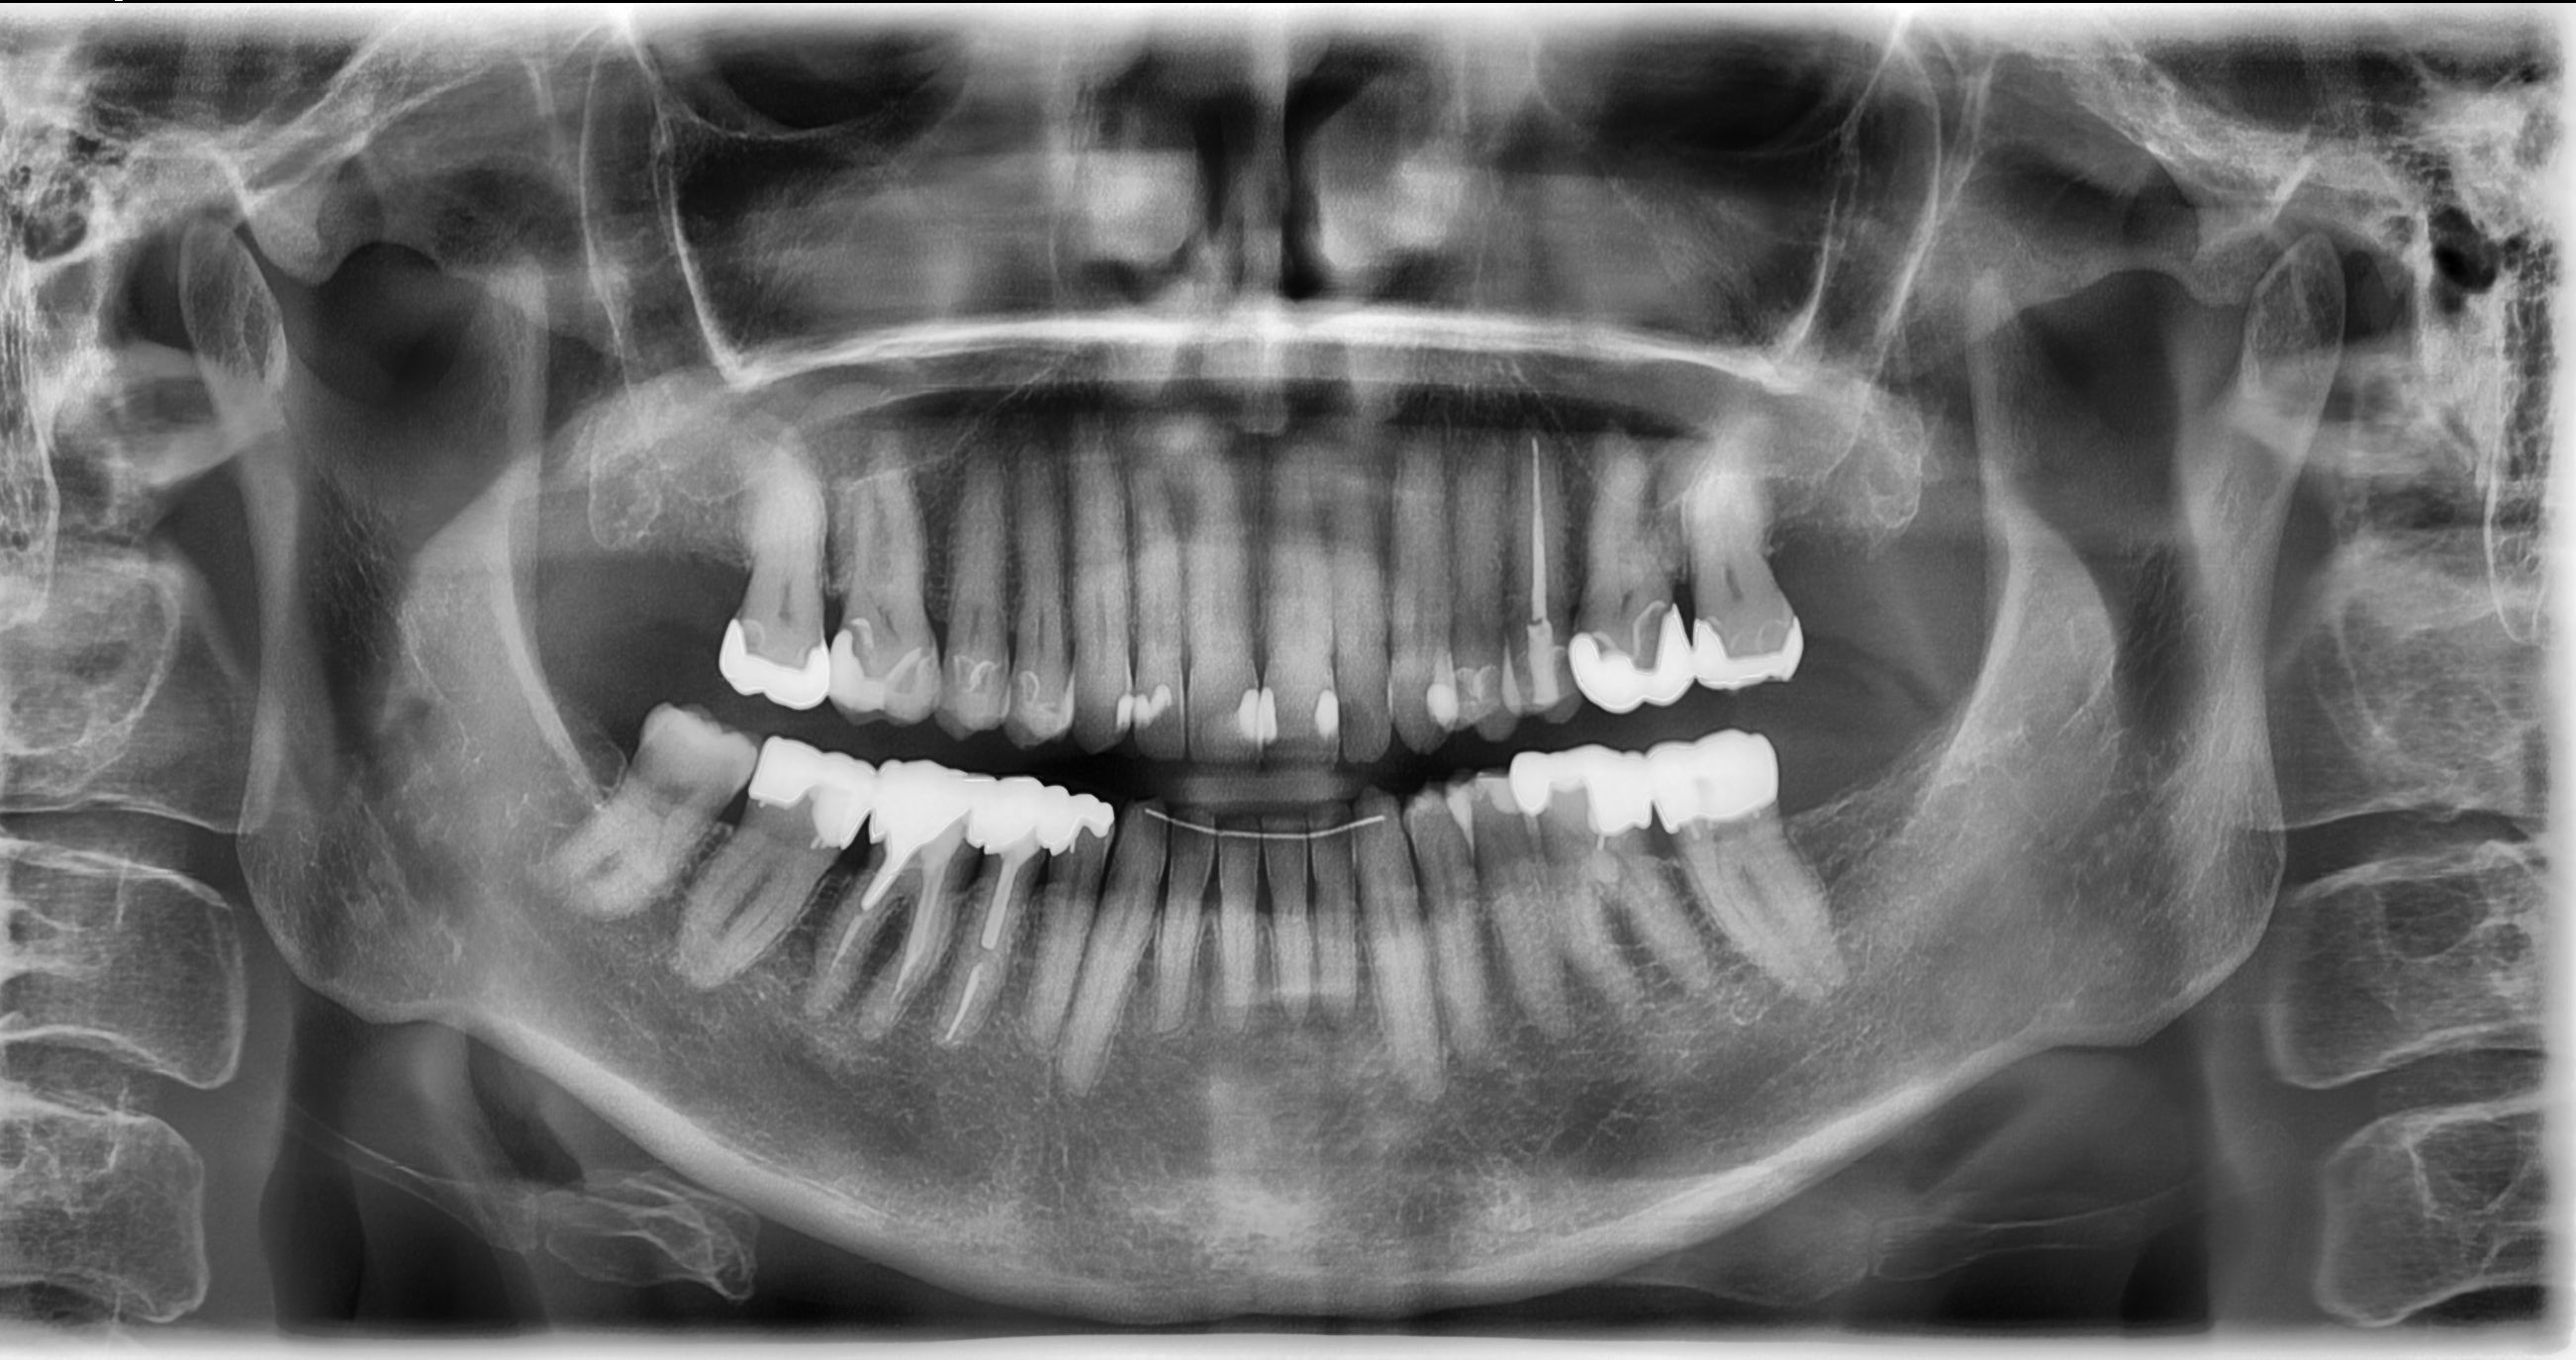

Teilkronen und ein Inlay

Ich bin Herrn Dr. xxx sehr dankbar. Er hat sich meine Zähne angeschaut und die mitgebrachten Röntgenbilder. Er war total begeistert von meinen alten Kronen und hat mir versichert, dass daran überhaupt nichts gemacht werden muss. Unfassbar, dass mir ein anderer Zahnarzt alles erneuern wollte.